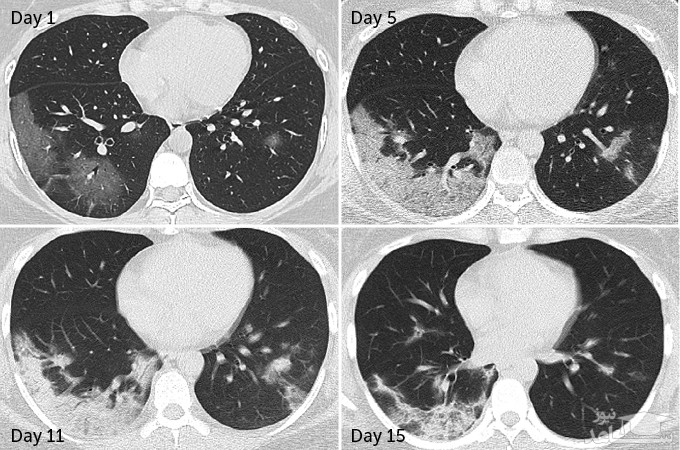

وانگ و همکاران گفتند این سی تی اسکن از یک زن ۳۵ ساله مبتلا به ویروس کروناست که نشان داده است برخی از آسیب های ریه حتی پس از بهبودی باقی می ماند.

همانطوری که مشاهده می کنید، هنگامی که این بیمار در بیمارستان بستری شد یک اسکن نشان داد که بافت یا مایعات باعث انسداد رگ های خونی در هر دو ریه می شود.

برخی از بافت ها تا روز پانزدهم، چند روز قبل از اینکه بیمار از بیمارستان ترخیص شود، بهبود یافتند، اما برخی از این بافت ها ممکن است در ریه ماندگار شوند؛ بنابراین با توجه به گسترش وسیع این بیماری همه گیر، مشکلات ریوی ناشی از کووید ۱۹ ممکن است سلامتی هزاران نفر را در سال های بعد تهدید کند.